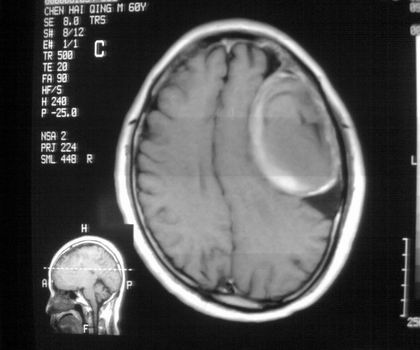

以下是引用影像孺子牛在2008-4-29 21:20:00的发言:[br]首先病变定位在脑外,根据ct密度及mri信号特征考虑慢性硬膜下血肿不连续环形钙化。

以下是引用周战梅在2008-4-29 23:12:00的发言:[br]脑外病变,蛛网膜下腔增宽,囊壁点状、环形钙化,增强扫描呈不均匀环状强化,考虑为囊性脑膜瘤可能性大,慢性脓肿、血肿机化、胆脂瘤不能除外。